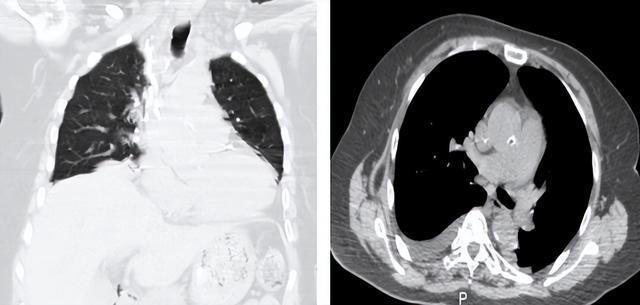

(▲术后复查CT疝入胸腔的肠管已完全回纳腹腔,被压迫的右肺成功复张)

术后,李奶奶恢复良好,呼吸困难症状消失,在不吸氧的情况下,血氧饱和度稳定在95%以上,现已康复出院。